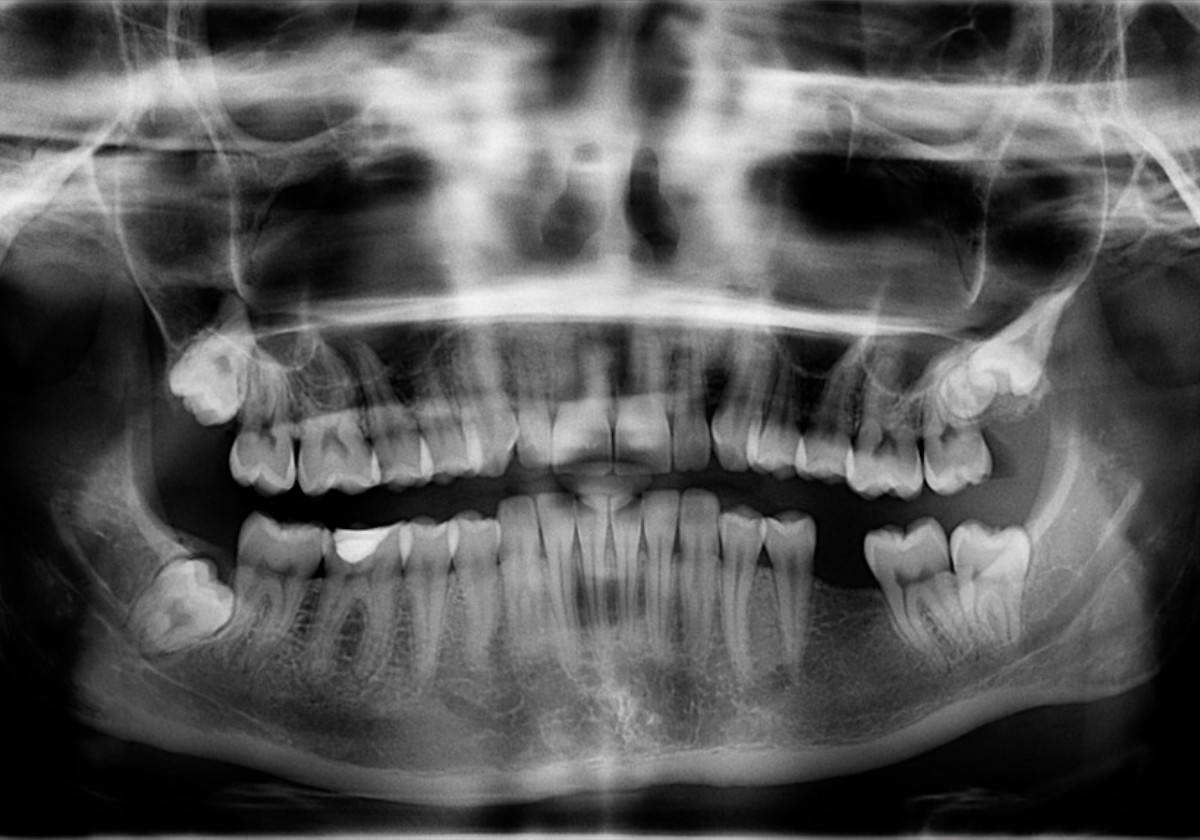

X-rays are an essential part of any dental care treatment plan. They are diagnostic, but they can also be preventative, by helping a dentist diagnose potential oral care issues in a patient’s mouth before they become a major problem.

X-rays allow us to:

• Find cavities

• Look at the tooth roots

• Check the health of the bony area around the tooth

• Determine if periodontal disease is an oral care issue

• See the status of developing teeth

• Monitor good tooth health